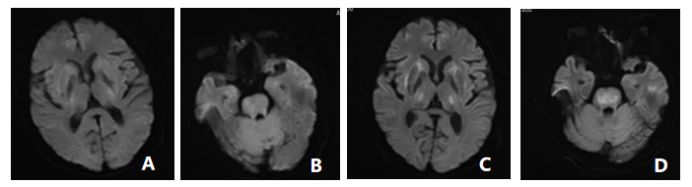

2023年1月,我科收治1例病人,当时病人病情很重,昏迷、四肢瘫痪,前期2次行MRI检查未见病灶(图A、B),腰椎穿刺脑脊液检查未见异常,结合患者有低钠血症病史,考虑渗透性脱髓鞘综合征,1周后再次复查头颅MRI桥脑、双侧基底节区多发病灶显示(图C、D),给予激素冲击、免疫球蛋白、高压氧疗、营养支持及积极的康复训练等综合治疗,在医护人员和家属的共同努力下,最终,患者意识清楚,可独立行走。此病例对提高临床医师对该病的认识、早期预防及诊治具有十分重要的意义,以下将做一个简短介绍。

ODS在CT上表现为脑桥中央或脑桥外病灶处的低密度影,但CT不能反映疾病的真实程度,MRI能更好地反映病灶的数量和程度。早期可无异常,出现症状后1周DWI上可发现高信号。各序列均可出现异常信号,FLAIR显示病灶高信号更清楚,DWI对于CPM的早期诊断较为敏感,CPM患者发病24h内即可在脑桥出现异常的高信号,呈典型的“蝙蝠翼”或“三叉戟”样改变,在出现临床症状约1个月后,DWI弥散受限高信号逐渐减低。皮质层及皮质下也可出现异常信号。